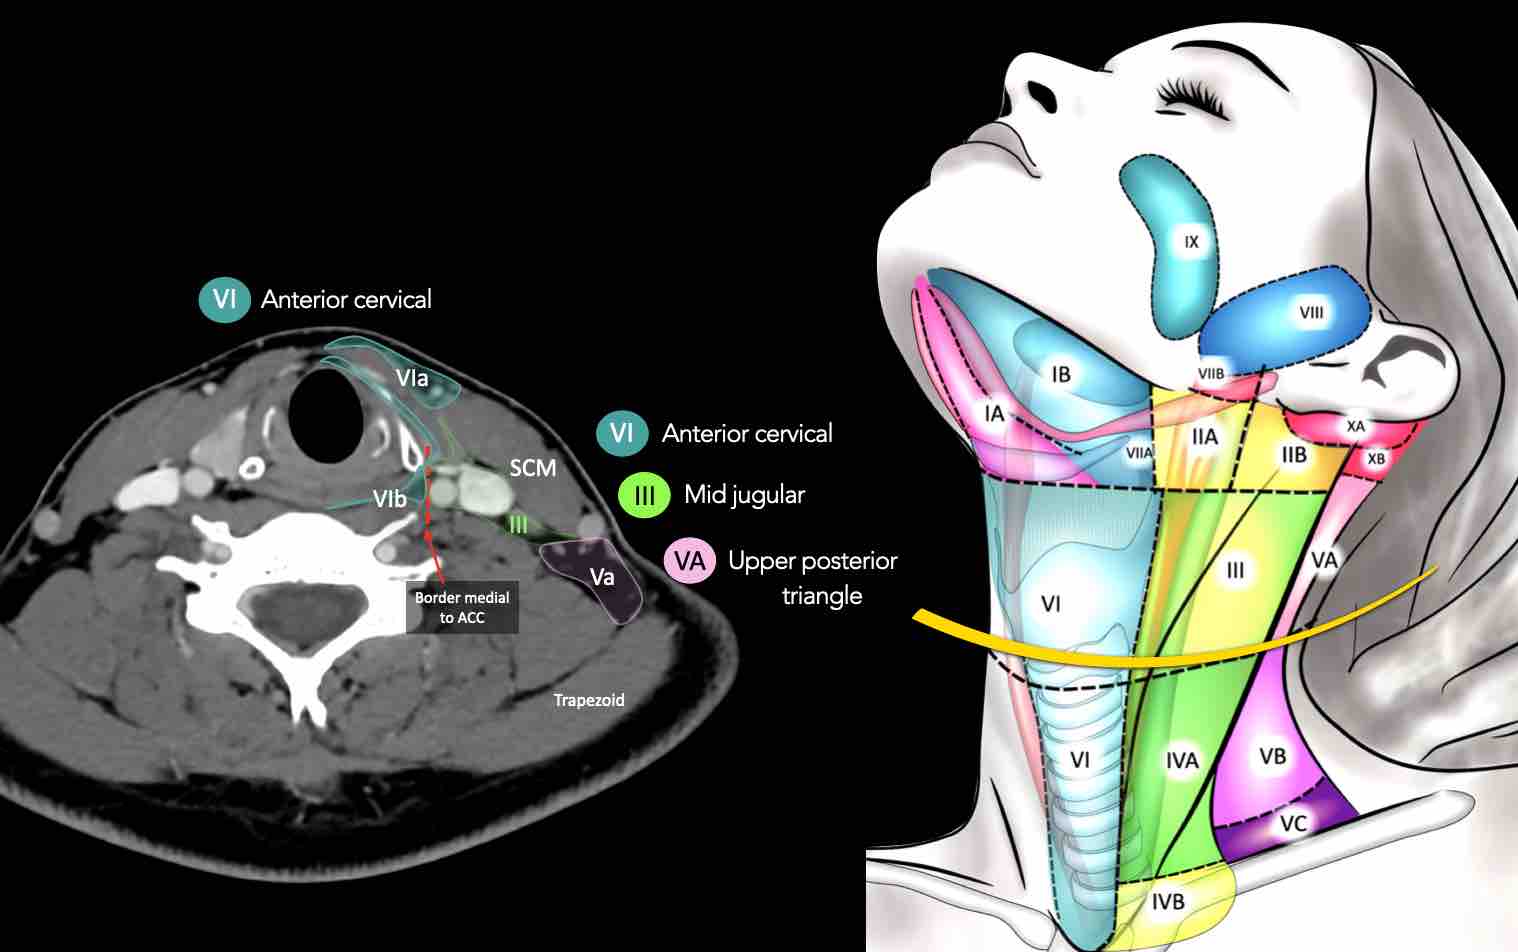

CT Scan Mặt Cắt Ngang (Axial CT)

Các lát cắt CT mặt phẳng ngang tương ứng với hình minh họa tổng quan.

Các lát cắt CT mặt phẳng ngang với hình ảnh chi tiết hơn.

Nhấp vào hình ảnh để phóng to.

III – Tĩnh mạch cảnh giữa

Tầng III nhận các bạch mạch hướng tâm từ tầng II và V, và một số bạch mạch hướng tâm từ các hạch sau hầu, trước khí quản và thần kinh thanh quản quặt ngược.

Tầng này thu nhận bạch huyết từ đáy lưỡi, amidan, thanh quản, hạ hầu và tuyến giáp.

Bờ dưới của sụn nhẫn là ranh giới giữa tầng III và tầng IVA.

Các hạch bạch huyết ở tầng III có nguy cơ chứa di căn từ các ung thư khoang miệng, vòm hầu, hầu miệng, hạ hầu và thanh quản.

VI – Cổ trước

Tầng này chứa các hạch tĩnh mạch cảnh trước nông (tầng VIa) và các hạch sâu hơn bao gồm hạch trước thanh quản, trước khí quản, cạnh khí quản và hạch thần kinh thanh quản quặt ngược (tầng VIb).